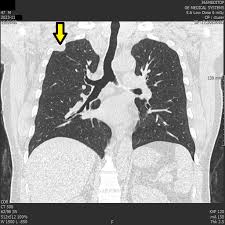

🔎 폐결절 진단 절차

- 흉부 X‑선 또는 흉부 CT로 발견

- 이전 영상과 비교하여 결절의 변화 여부 확인

- 결절 크기·형태·경계·석회화 여부 등 특징 분석

- 의심되는 경우 PET-CT 스캔 또는 조직 생검 시행